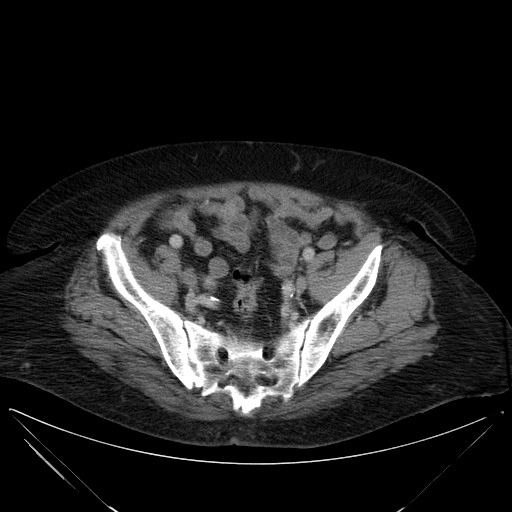

Gãy xương chậu (Pelvic fractures)

16/03/2026